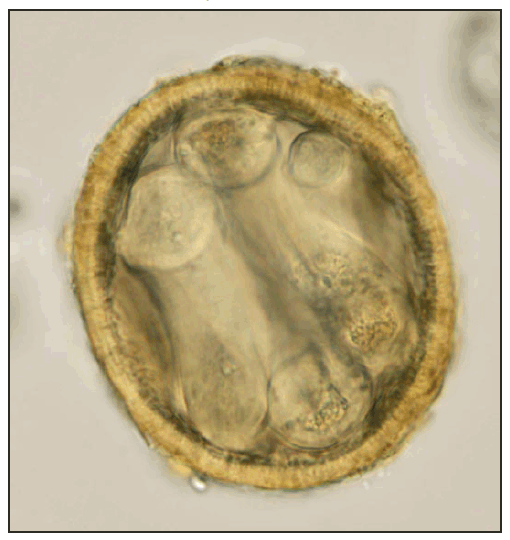

Fecal samples from animals in each of the 21 enclosures were examined, and no BP eggs were found. During a subsequent USDA-AC visit, soil samples were collected from under the breeding cages of the two juveniles sent to Tennessee. Samples (weighing 40--50 g) from each of the two bags of soil were processed and examined for eggs. Infective (larvated) BP eggs (Figure 2) were found in both samples, with one being heavily contaminated.

FIGURE 2. Infective (larvated) Baylisascaris procyonis egg uncovered from the soil under a kinkajou cage --- Florida, April 2010

Photo/K. Kazacos

Alternate Text: The figure above shows an infective (larvated) Baylisascaris procyonis egg, uncovered from the soil under a kinkajou cage in Florida in April of 2010.